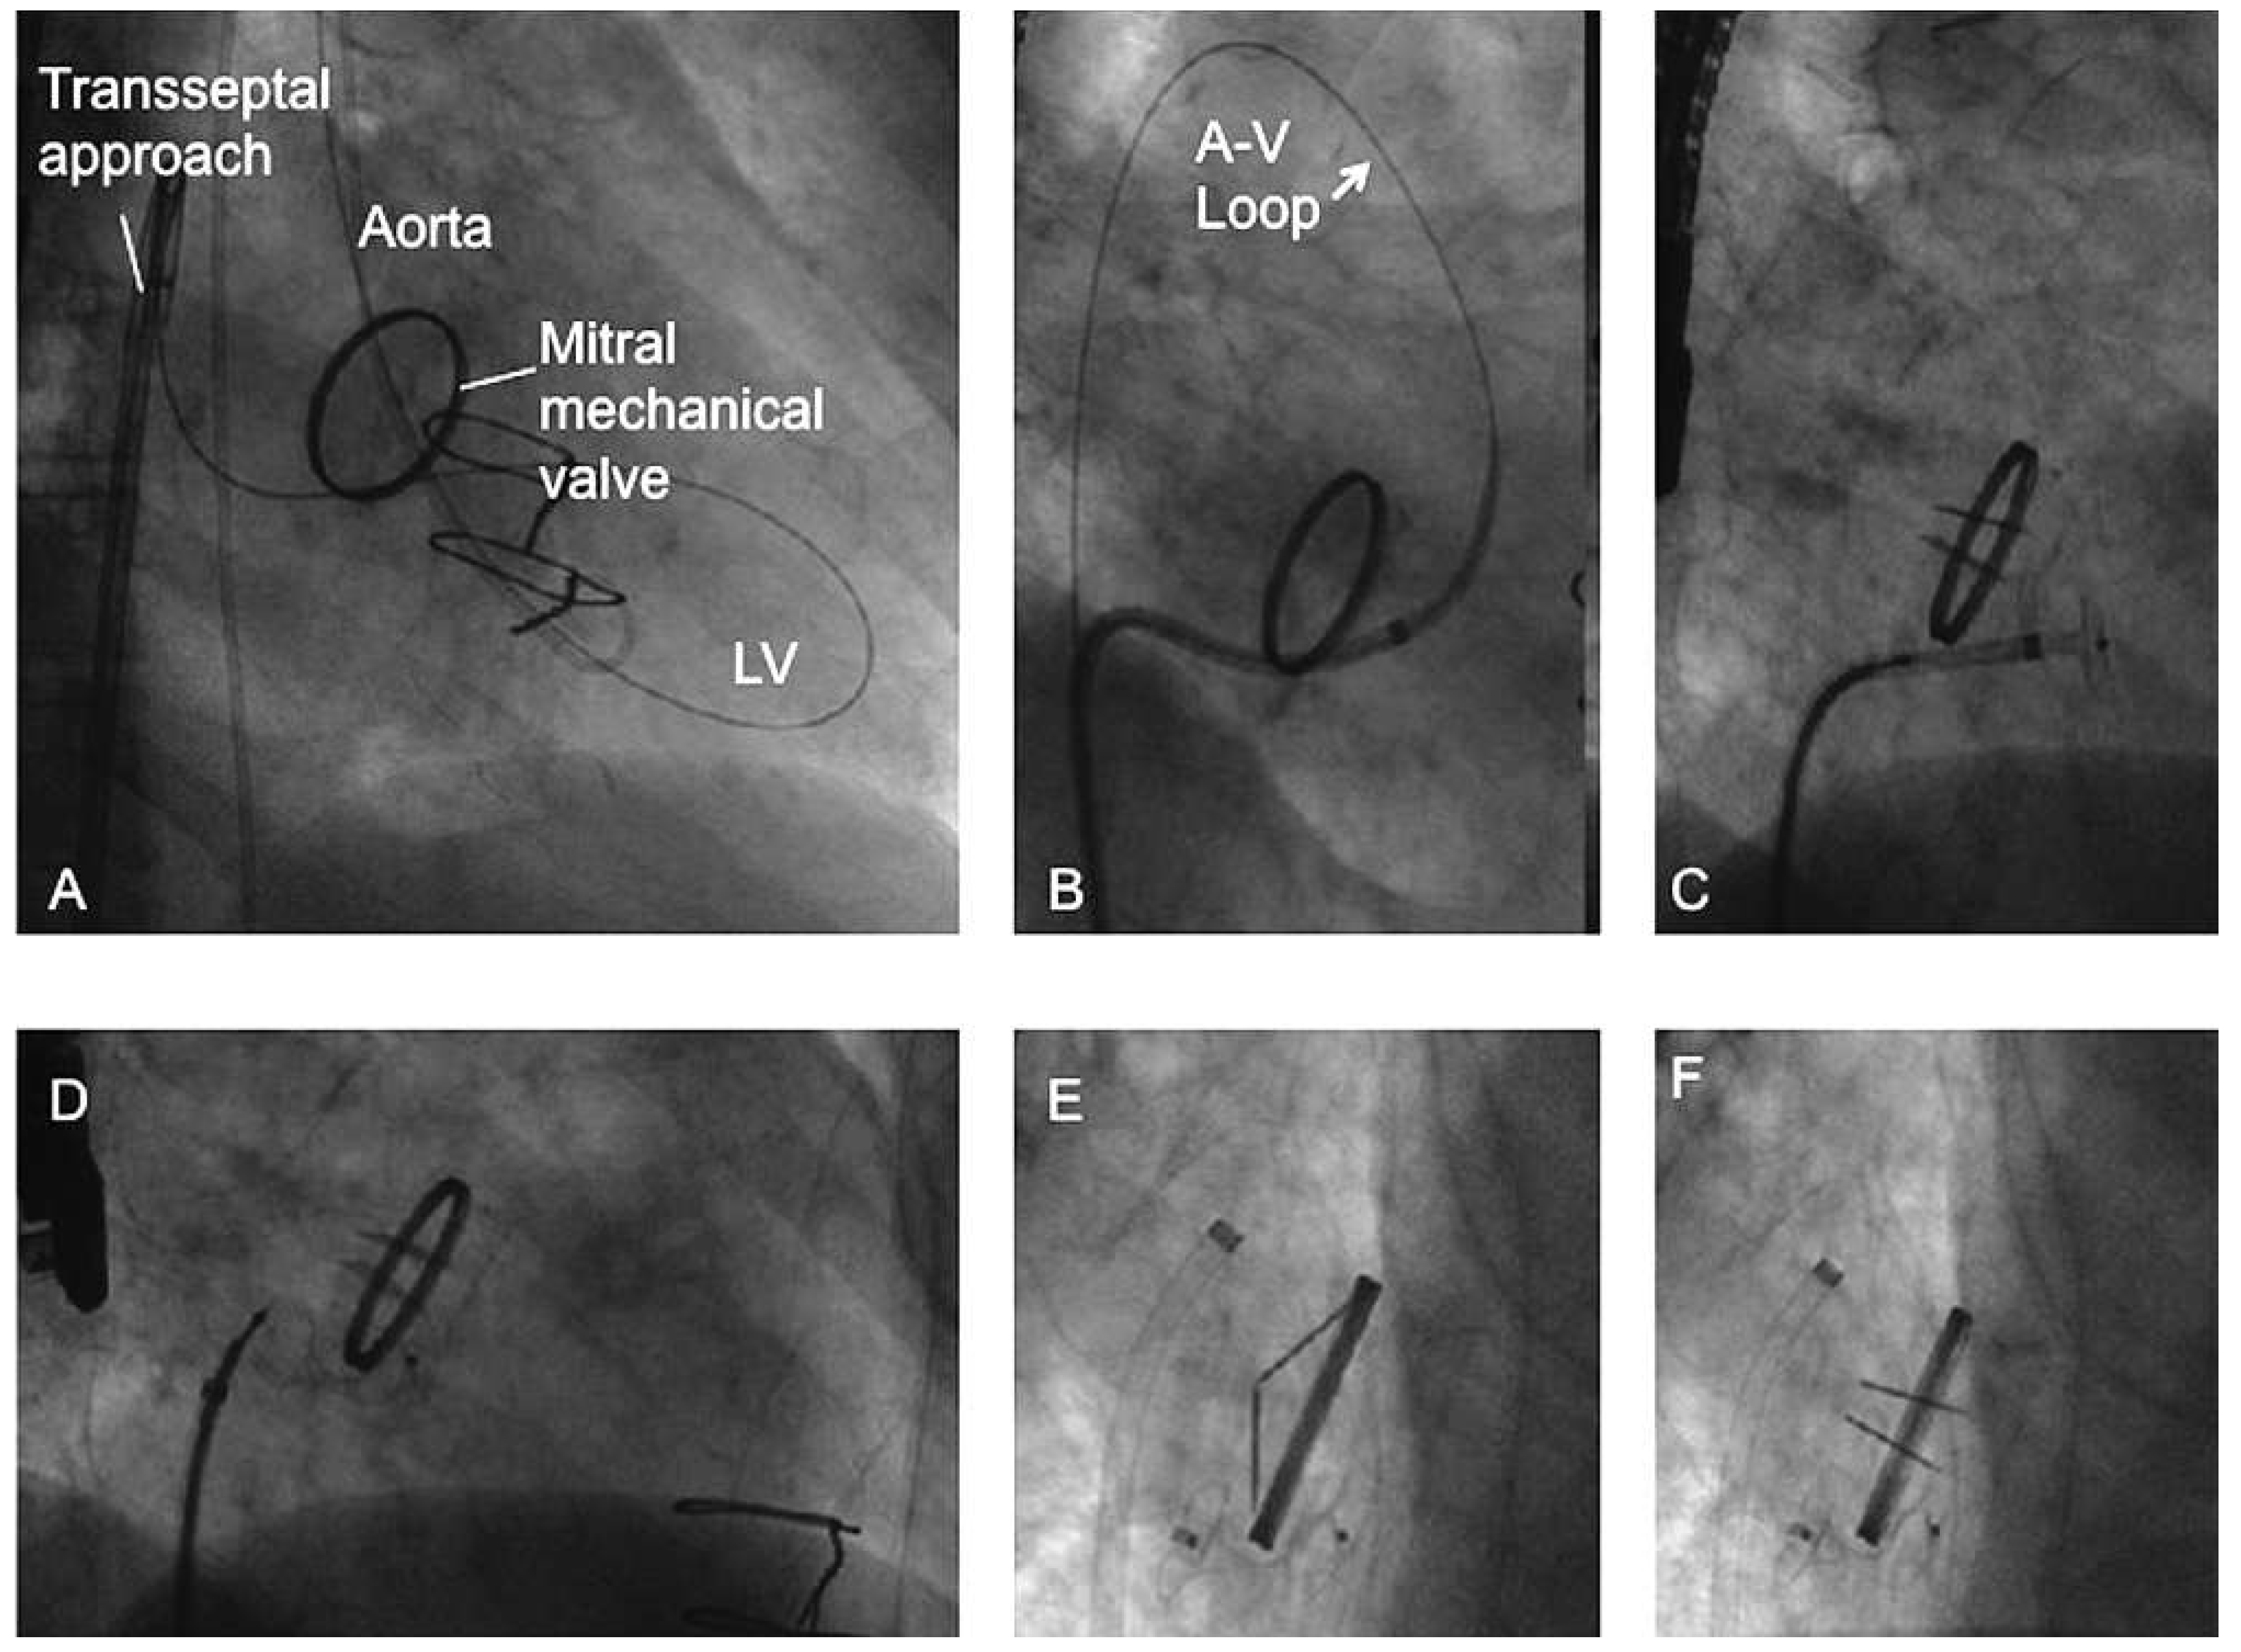

Considerations for mitral paravalvular leak

Alternative approach